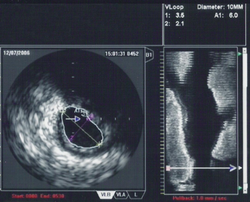

An intravascular ultrasound image of the ostium of the left main coronary artery

Intravascular ultrasound, also known as a percutaneous echocardiogram is an imaging methodology using specially designed, long, thin, complex manufactured catheters attached to computerized ultrasound equipment to visualize the lumen and the interior wall of blood vessels.